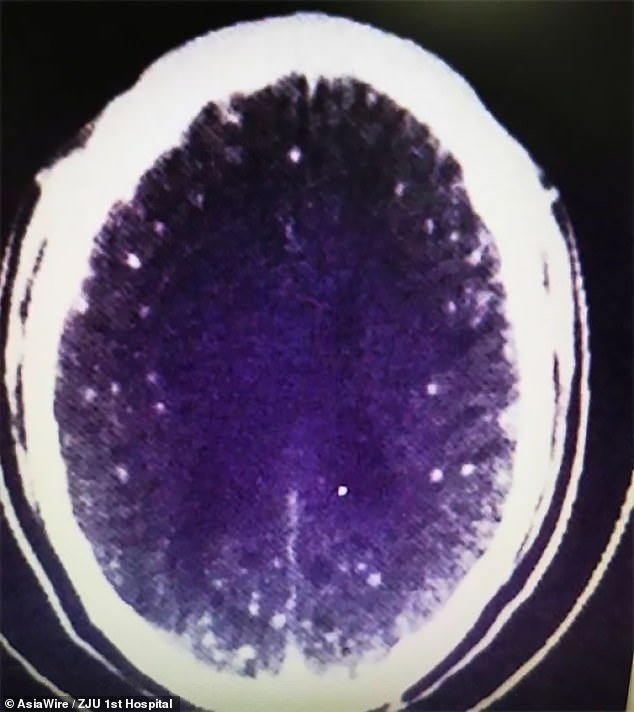

एजेन्सी । चीनका ४६ वर्षका झु जोन्गफाको शरीरमा ७ सय बढी परजीवी फित्ते जुका (टेपवर्म) भेटिएका छन् । यी जुका ती व्यक्तिको दिमागदेखि मृगौलासम्म पुगिसकेका थिए । स्थानीय आम सञ्चार मध्यमका अनुसार मजदुरी गर्ने झुलाई अस्पताल पुर्याउँदा उनले मुखमा फिँज निकालिरहेका थिए र बेहास थिए ।

उपचारको क्रममा उक्त फित्ते जुकाको अण्डा पेटसम्म पुगिसकेको र रगतमार्फत् शरीरभरी फैलिसकेको पत्ता लागेको छ । डाक्टरका अनुसार उक्त फित्ते जुका सुँगुरको मासुमार्फत् उनको शरीरभित्र प्रवेश गरेको र यसले आफ्नो संख्या बढाइरहेको थियो ।

झियांग युनिभर्सिटी अफ मेडिसिनसँग सम्बन्धित अस्पतालका डा. जियानरन्गका अनुसार दिमाग र छातीको स्क्यान गरिएको छ । रिपोर्टमा भित्ते जुकाको पुष्टि भएको छ । मष्तिस्कबोहक फोक्सो र टाउकोको मांसपेशीमा पनि यी देखिएका छन् । डा. हुआंगका अनुसार एन्टी प्यारासाइटिक औषधी दिएर जुका र लार्भालाई मारिइसकिएको छ तर उपचार भने पूरा भएको छैन । यसको असर कतिसम्म हुन्छ त्यसबारे यकिन गर्न नसकिने डाक्टरले बताए ।